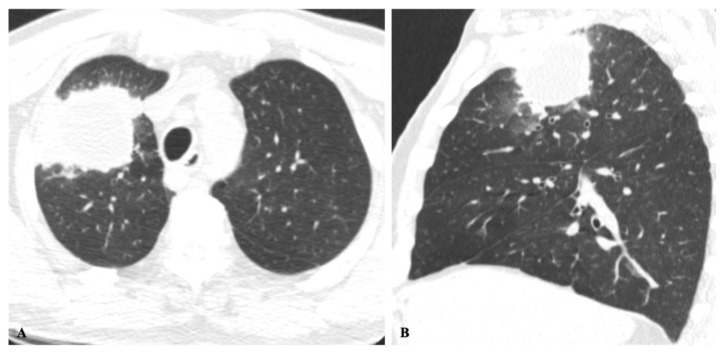

Endemic fungal infections are responsible for high rates of morbidity and mortality in certain regions of the world. The diagnosis and management remain a challenge, and the reason could be explained by the lack of disease awareness, variability of symptoms, and insidious and often overlooked clinical presentation. Imaging findings are nonspecific and frequently misinterpreted as other more common infectious or malignant diseases. Patient demographics and clinical and travel history are important clues that may lead to a proper diagnosis. The purpose of this paper is to review the presentation and differential diagnosis of endemic mycoses based on the most common chest imaging findings.